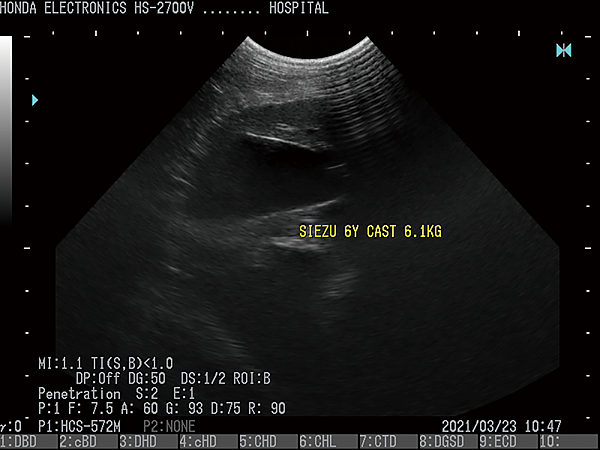

- 通過H-res獲得清晰豐富的單色圖像

HONDA獨創的圖像增強技術 H-res(我們的分辨率技術)

多年來超聲波技術的發展,結晶為“ H-res”圖像增強技術。

可以通過針對每種應用和探頭調整“ H-res”參數來獲得最佳圖像。